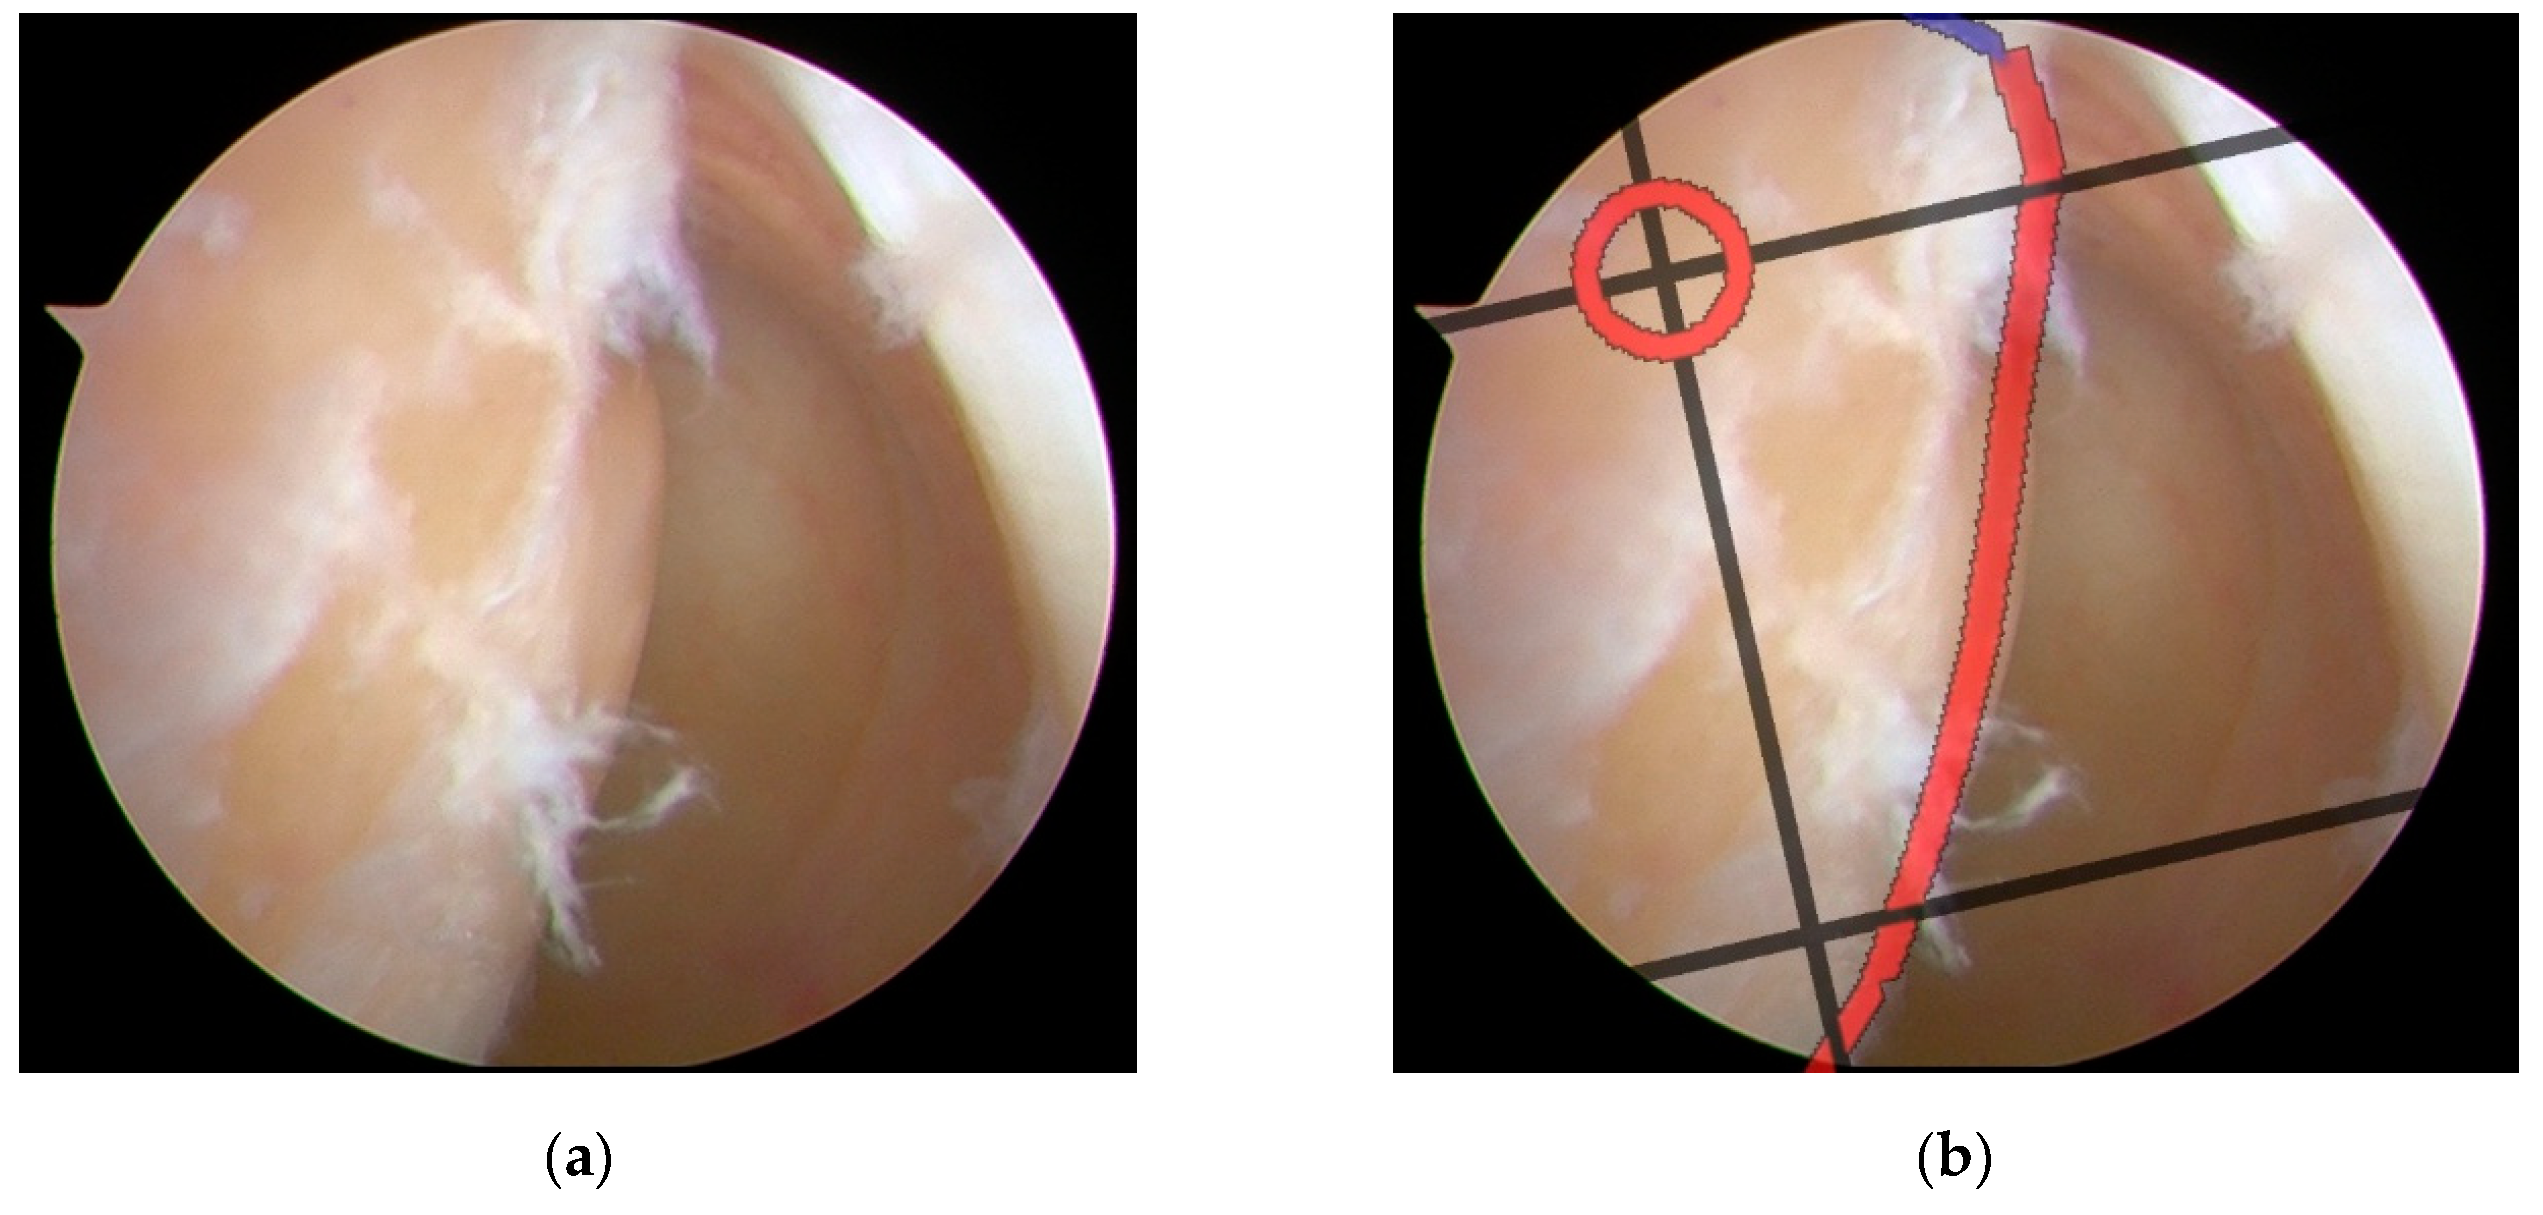

2.6. Real-time B&H Grid Overlay

3.1. Expert Concordance